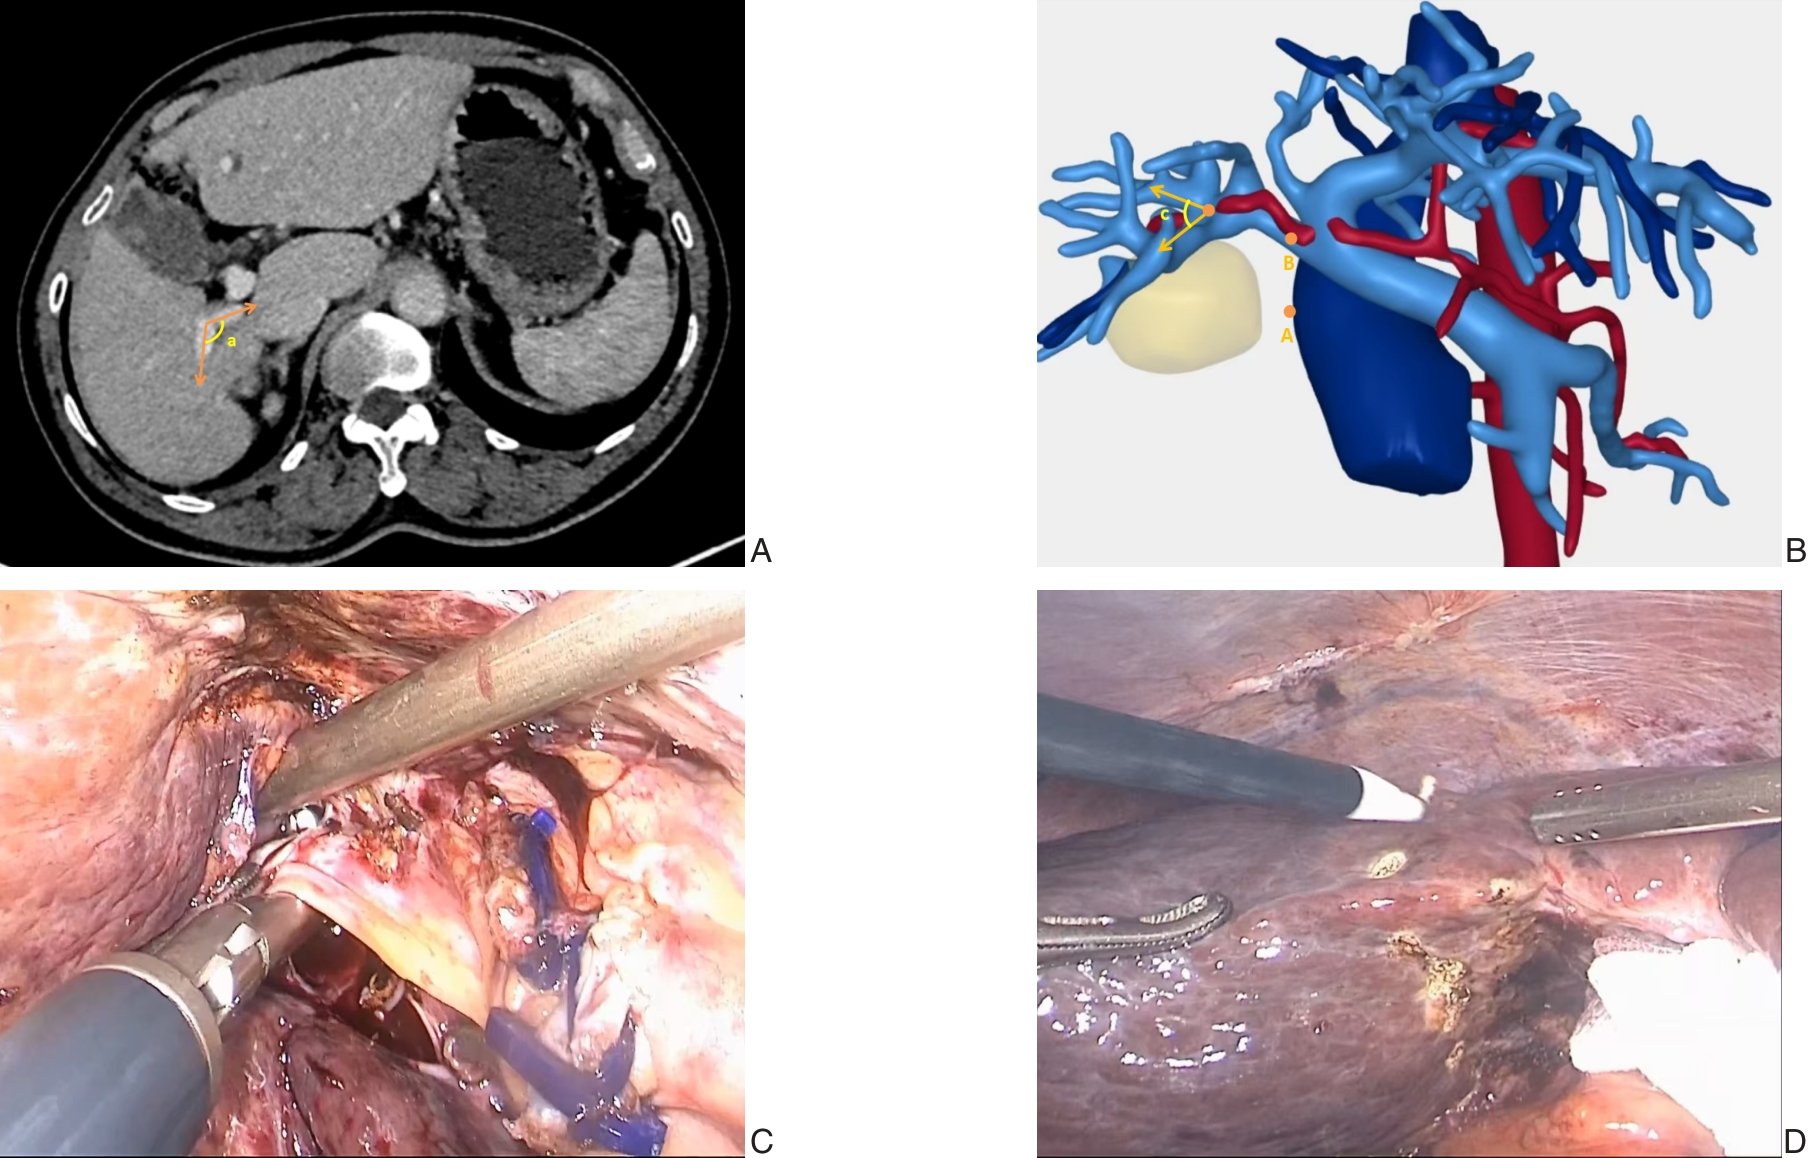

2026,35(1):88-96, DOI: 10.7659/j.issn.1005-6947.250468

Abstract:

Background and Aims Laparoscopic resection of centrally located hepatic tumors remains technically demanding due to the complex anatomical relationships with major vascular structures. Conventional intraoperative ultrasound or indocyanine green fluorescence imaging (ICG-FI) alone has limitations, particularly in visualizing deep anatomical structures. This study aimed to evaluate the clinical value of augmented reality (AR) navigation combined with ICG-FI in laparoscopic resection of central hepatic tumors.Methods A retrospective analysis was conducted on 38 consecutive patients who underwent laparoscopic resection of central hepatic tumors guided by AR navigation combined with ICG-FI between May 2022 and March 2025. Intraoperative navigation performance, surgical parameters, and perioperative outcomes were assessed.Results All 38 procedures were completed laparoscopically without conversion. The intraoperative tumor fluorescence detection rate was 100%. The mean operative time was (324.9 ± 132.4) min, and the median intraoperative blood loss was 400 (50-1 200) mL. The mean registration error was (6.3±0.6) mm. The median number of predicted and verified vessels was 6 (4-8) and 7 (5-10), respectively. R0 resection was achieved in all patients, with a mean surgical margin of (1.5±0.5) cm. The postoperative complication rate was 13.2%, with no severe complications such as intra-abdominal hemorrhage, gas embolism, or liver failure. The median postoperative hospital stay was 9 (4-20) days. During a median follow-up of 20 months, no tumor recurrence was observed.Conclusion The combined use of AR navigation and ICG-FI enables intraoperative prediction and verification of critical vascular structures and facilitates precise control of the transection plane in laparoscopic resection of central hepatic tumors. This technique improves surgical precision and safety and shows promising clinical potential.